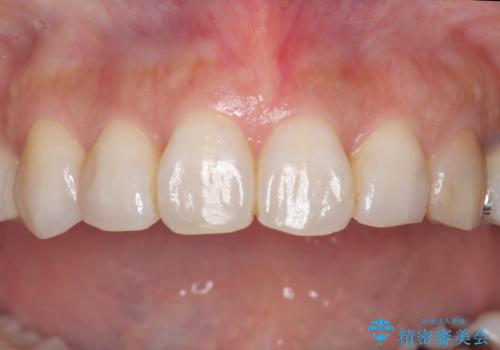

治療途中

左:虫歯を除去したところ。遠心が歯ぐきより深い状態です。中:そのままかぶせようとすると、遠心が歯ぐきが腫れやすい状態です。右:エクストリュージョンをしたことで、遠心の歯ぐきの腫れが収まっていることがわかります。